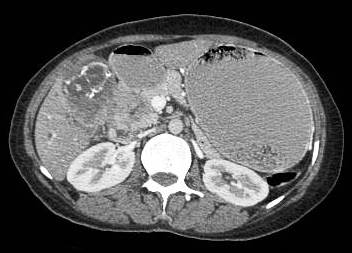

Common patterns of carcinoma gallbladder

Three patterns have been described on ultrasonography (US). The gallbladder fossa is replaced by a heterogeneous mass (figure 1) with internal areas of necrosis; or there may be diffuse, irregular, and asymmetrical wall thickening (Figure 2); or less commonly, a polypoidal, fungating intra-luminal mass is seen. Correct preoperative diagnosis has improved considerably with the use of newer imaging techniques [6-8]. Majority of cases when diagnosed, are no longer resectable (Figure 3) [9-11].

Figure 1: large gallbladder fossa mass replacing the entire gall bladder. Discrete liver secondaries can be seen.

Figure 1: Large gallbladder fossa mass replacing the entire gallbladder. Discrete liver secondaries can be seen.